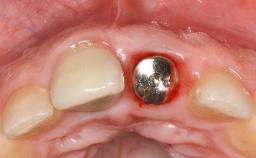

Treatment of Peri-Implant Mucositis at a Zirconia Implant